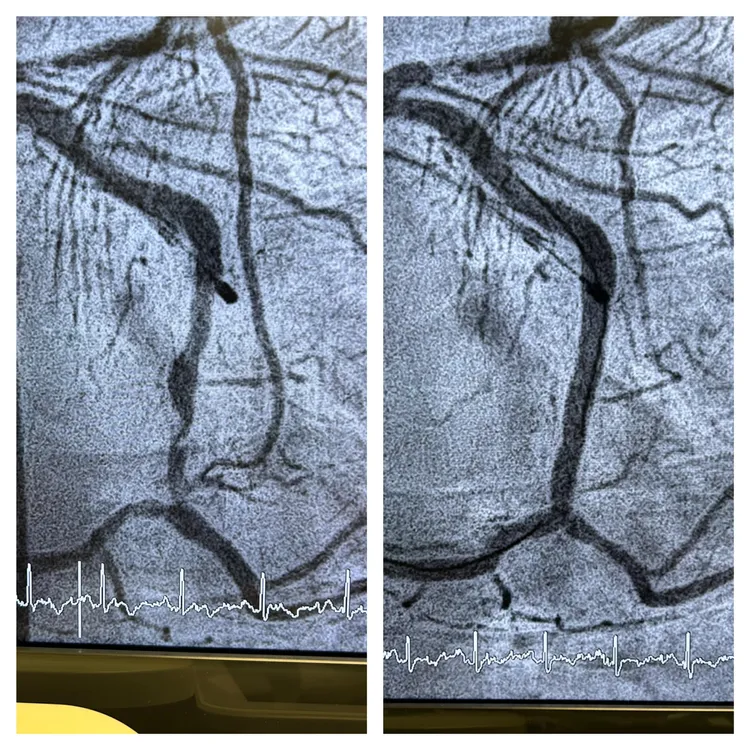

「不做不知道,一做嚇一跳」陳冠任說,她的心電圖竟然呈現急性心肌梗塞,必須立即做緊急心導管手術,告知道若不馬上打通心臟血管,會有生命危險,要她馬上聯絡小孩,立刻來醫院。

陳冠任表示,術後發現大姐有兩條血管狹窄超過九成以上,不處理隨時會有猝死的可能,幸好手術順利目前兩條都已暢通,人的症狀也改善許多。他表示,該患者術後仍要乖乖控制高到爆表的壞膽固醇,不然根源問題未除,血管病變還是會反覆發生的,不是每次都能像這次這麼幸運。